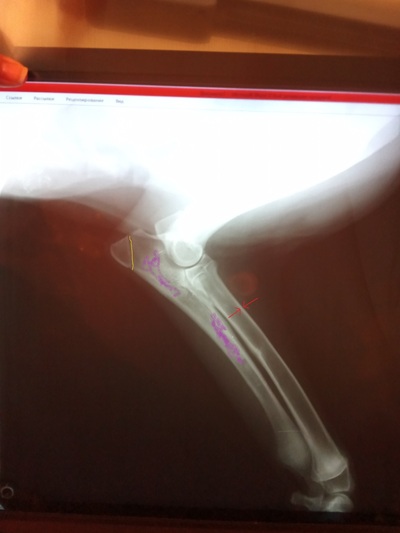

Клиника отдала мне оригиналы снимков, у них снимки только умеет делать рентген. Залил фото снимков на гугл.диск:

15 декабря примерно:

https://drive.google.com/file/d/1xLXBgF-A9EkaQEcYnz70CIhmz3-...

https://drive.google.com/file/d/1XtUZ_A5pP6sWWCSJjFr9AXJkzPA...

конец января:

https://drive.google.com/file/d/1PBm-ZrvmQlNTYObeOk4UMaEPZc9...

Пришлось заходить с компьютера, что бы хорошо посмотреть снимки. Скорее всего трещину перепутали с зоной роста (отметил желтым). Наличие зон роста - это не проблема. По рентгену определяются участки костей с явным признаком воспалительного процесса (паностеит, отметил фиолетовым), рекомендовал бы рентгенографическое исследование контрлатеральной конечности, так же есть снижение кортикального слоя (отметил красным), стоит поискать проблемы в питании (возможно, с натуральной еды, перейти на некоторое время на коммерческие корма). Плюс, что бы меньше болело, назначаются противовоспалительные препараты на длительное время